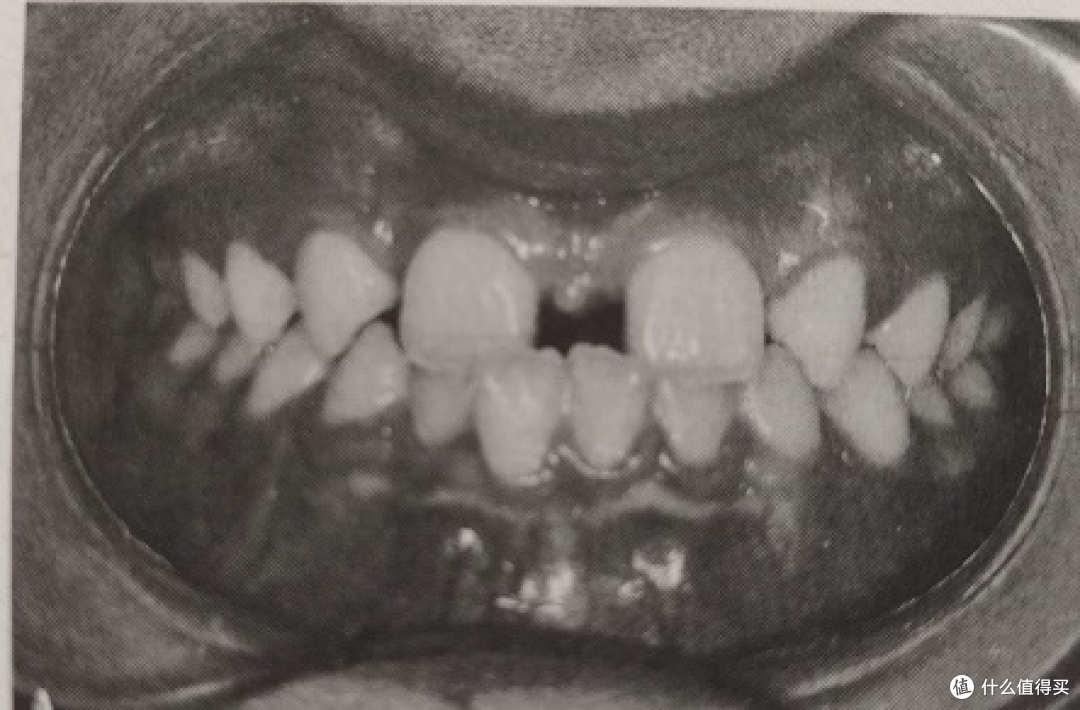

先天缺牙造成深咬的問題利用矯正與植牙恢復正常咬合 數位隱形牙齒矯正植牙牙齒美容速套微笑貝齒 碧礽 隨意窩

下牙套9个月后对比 门牙突 天生缺4颗牙 牙齿矫正